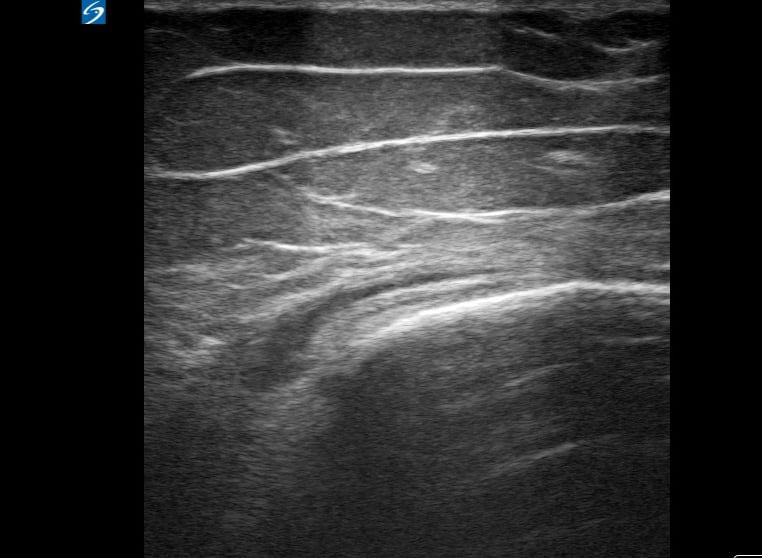

Diagnosing bursitis medically often involves clinical examination and imaging. Ultrasound is a valuable tool in its diagnosis and management, allowing for clear visualization of the inflamed bursa, its fluid content, and surrounding tissue changes. This helps differentiate bursitis from other conditions, guiding effective treatment strategies.